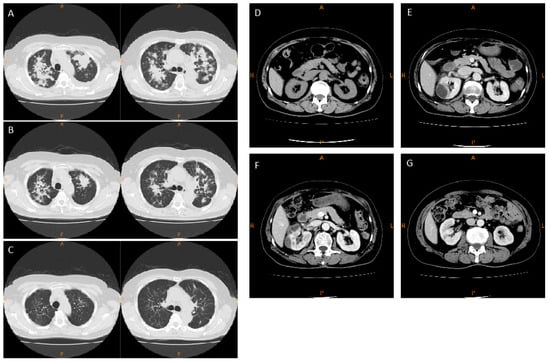

2.1. Case Report

2.2. Experimental Animal Model

2.2.1. Mesangial Expansion in Crizotinib-Treated Mouse

2.2.2. Crizotinib Caused Renal Histopathological Changes